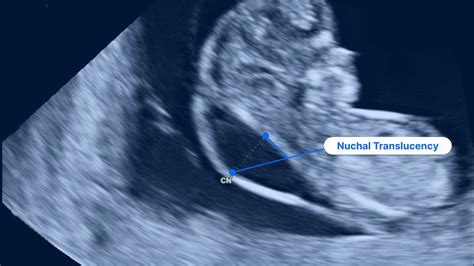

Prenatal screening is a crucial aspect of modern obstetrics, providing expectant parents with valuable insights into their baby's health. One of the key components of early prenatal screening is the measurement of the nuchal translucency, a fluid-filled space at the back of the baby's neck. Understanding the nuchal translucency normal range is essential for interpreting these measurements and assessing potential risks.

The nuchal translucency (NT) measurement is typically performed during the first trimester of pregnancy, between 10 weeks and 13 weeks plus 6 days. This ultrasound scan assesses the thickness of the fluid behind the baby's neck. The measurement is crucial because an increased NT can indicate an elevated risk of certain chromosomal abnormalities, such as Down syndrome (Trisomy 21), Edwards syndrome (Trisomy 18), and Patau syndrome (Trisomy 13). Additionally, it can provide information about other potential issues, including heart defects and genetic syndromes.

The nuchal translucency normal range varies slightly depending on the gestational age of the fetus. Generally, the NT measurement should be less than 3.0 mm for most fetuses between 10 and 13 weeks plus 6 days. However, it is important to note that the normal range can be influenced by various factors, including the baby's crown-rump length (CRL) and the presence of any maternal risk factors.

Here is a general guideline for the nuchal translucency normal range based on gestational age:

Gestational Age (weeks) Nuchal Translucency Normal Range (mm)

10 1.0 - 2.5

11 1.1 - 2.6

12 1.2 - 2.7

13 1.3 - 2.8

It is crucial to remember that these are approximate ranges, and individual measurements should be interpreted by a qualified healthcare provider who can consider all relevant factors.